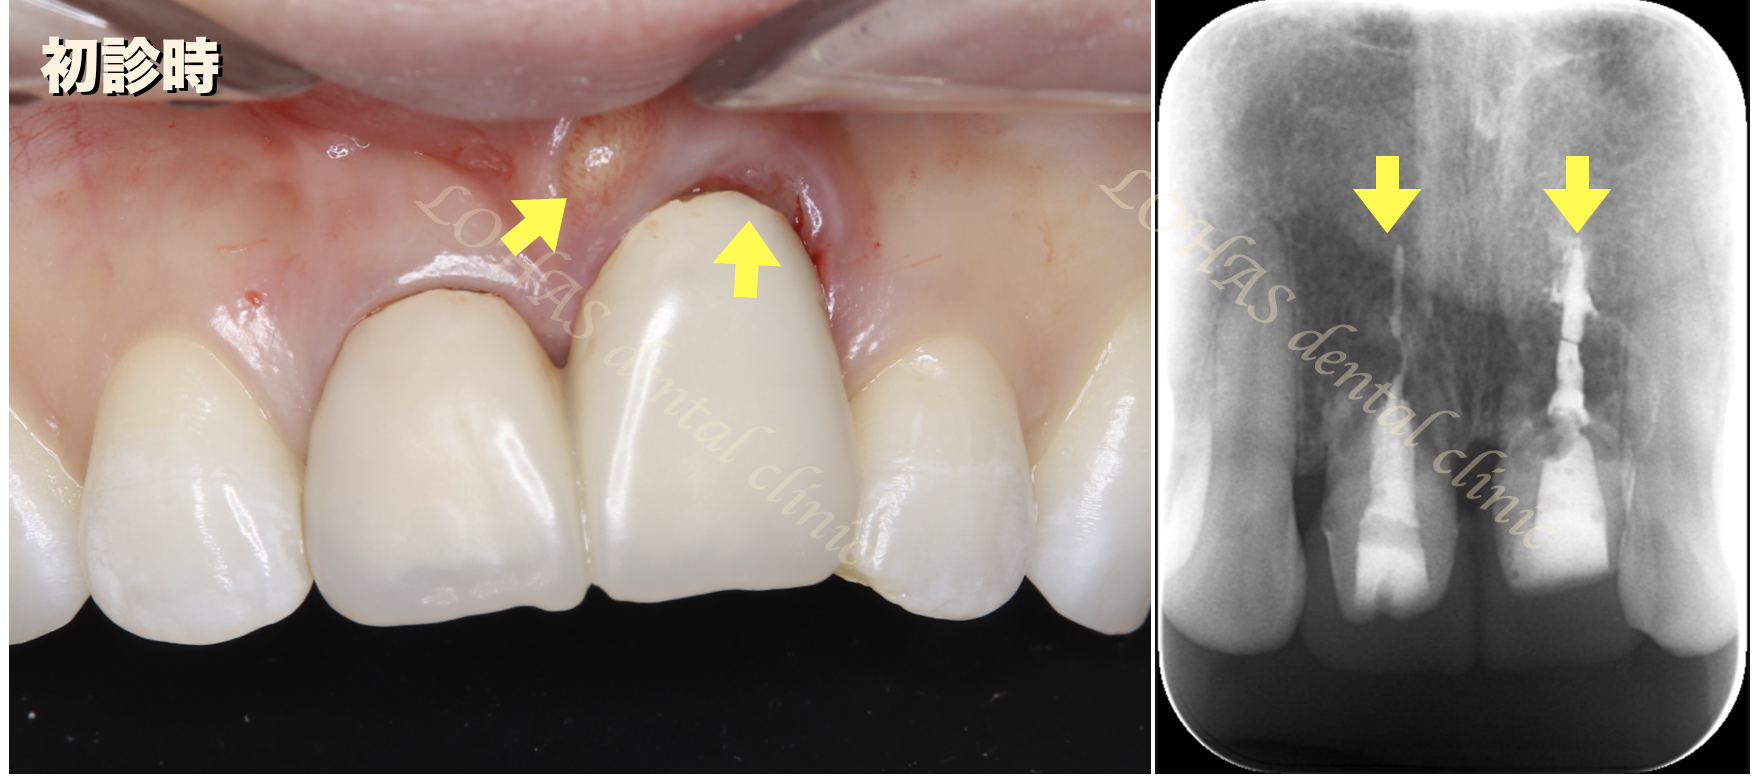

上顎の前歯2本は昔に外傷で、神経を取っており、差し歯になっていました。その歯の再治療は今までにも何回か繰り返していたそうなのですが、レントゲンではやはり歯を残しての治療は難しい状態でした。

慢性的な感染もあり、根の先端も溶けてしまっていたので、まずは抜歯を行いその後インプラント埋入と骨造成を行う治療計画を立てました。

矢印の部分に膿溜まっている事がわかります。

レントゲンを見ても根の先端が吸収を起こしており、再治療は不可能でした。